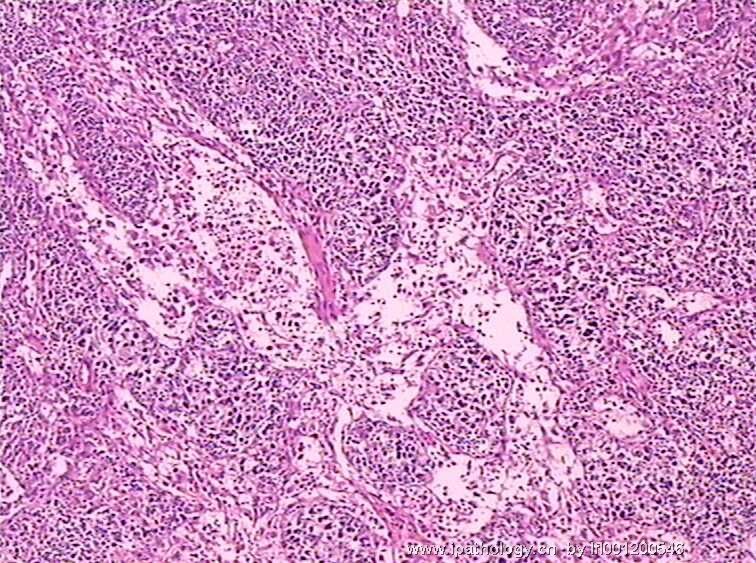

女,45岁,发现颈部多个淋巴结肿大,体查时发现全血细胞减少.取最大的淋巴结送检.

淋巴结结构破坏,有明显异常细胞,结合病史,考虑恶性,淋巴瘤、白血病?不知血片分类怎样?待组化和专家讲解。谢谢!

恶性,考虑淋巴造血系统肿瘤。NHL或白血病。

恶性是肯定,就是要排除转移的恶黑。再考虑原发的非何杰金